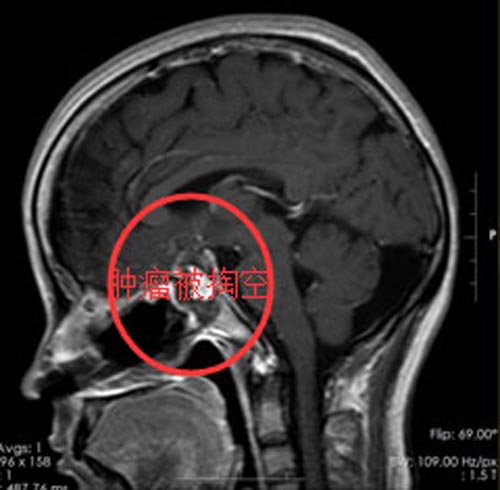

何丽女士出院时,视力有恢复,视野也清晰了。

▲手术后